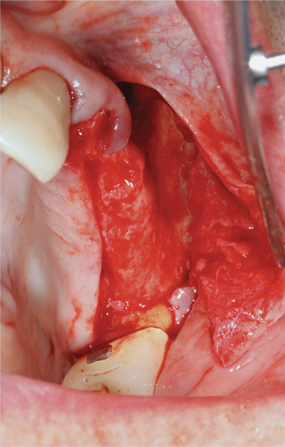

Fig 9. Atrophic maxillary left quadrant ridge prior to ridge augmentation.

Fig 10. Intraosseous penetrations prior to graft placement at maxillary left quadrant lateral ridge augmentation.